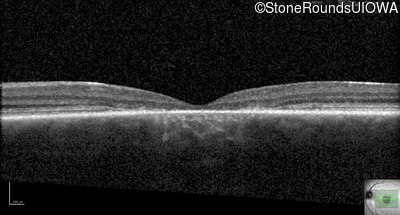

Optical Coherence Tomography - Left - 20/100

Exemplar / OCT Stack